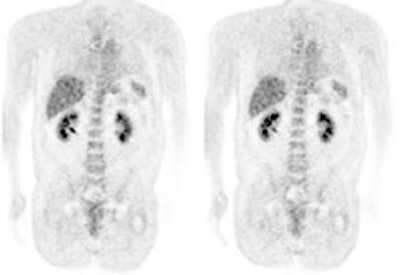

Hyperinsulinemia: The patient below had

a normal glucose level and was injected for an FDG PET

scan. Imaging revealed intense cardiac uptake and a large

about of muscular activity. The findings are consistent

with a hyperinsulinemic state and the patient subsequently

admitted to eating a small breakfast. |